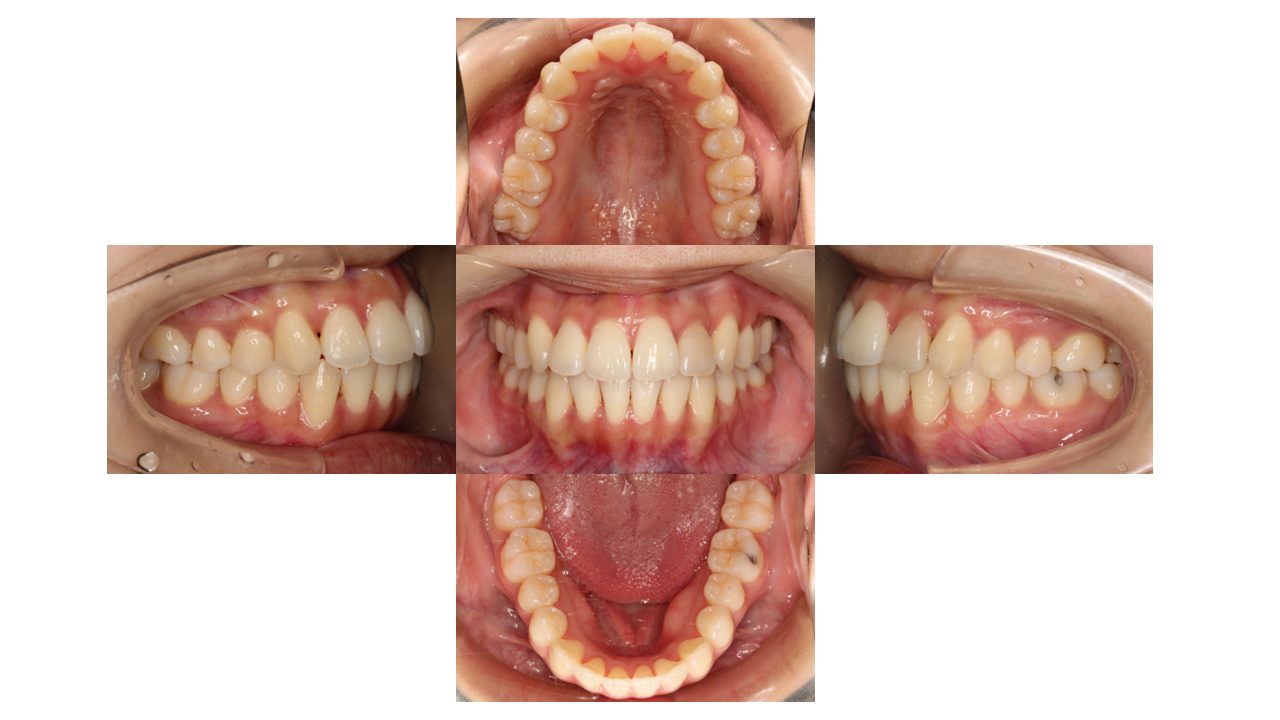

1年3か月経過のお口腔内の状態です。

上下前歯の凸凹が改善したとご満足いただけました。